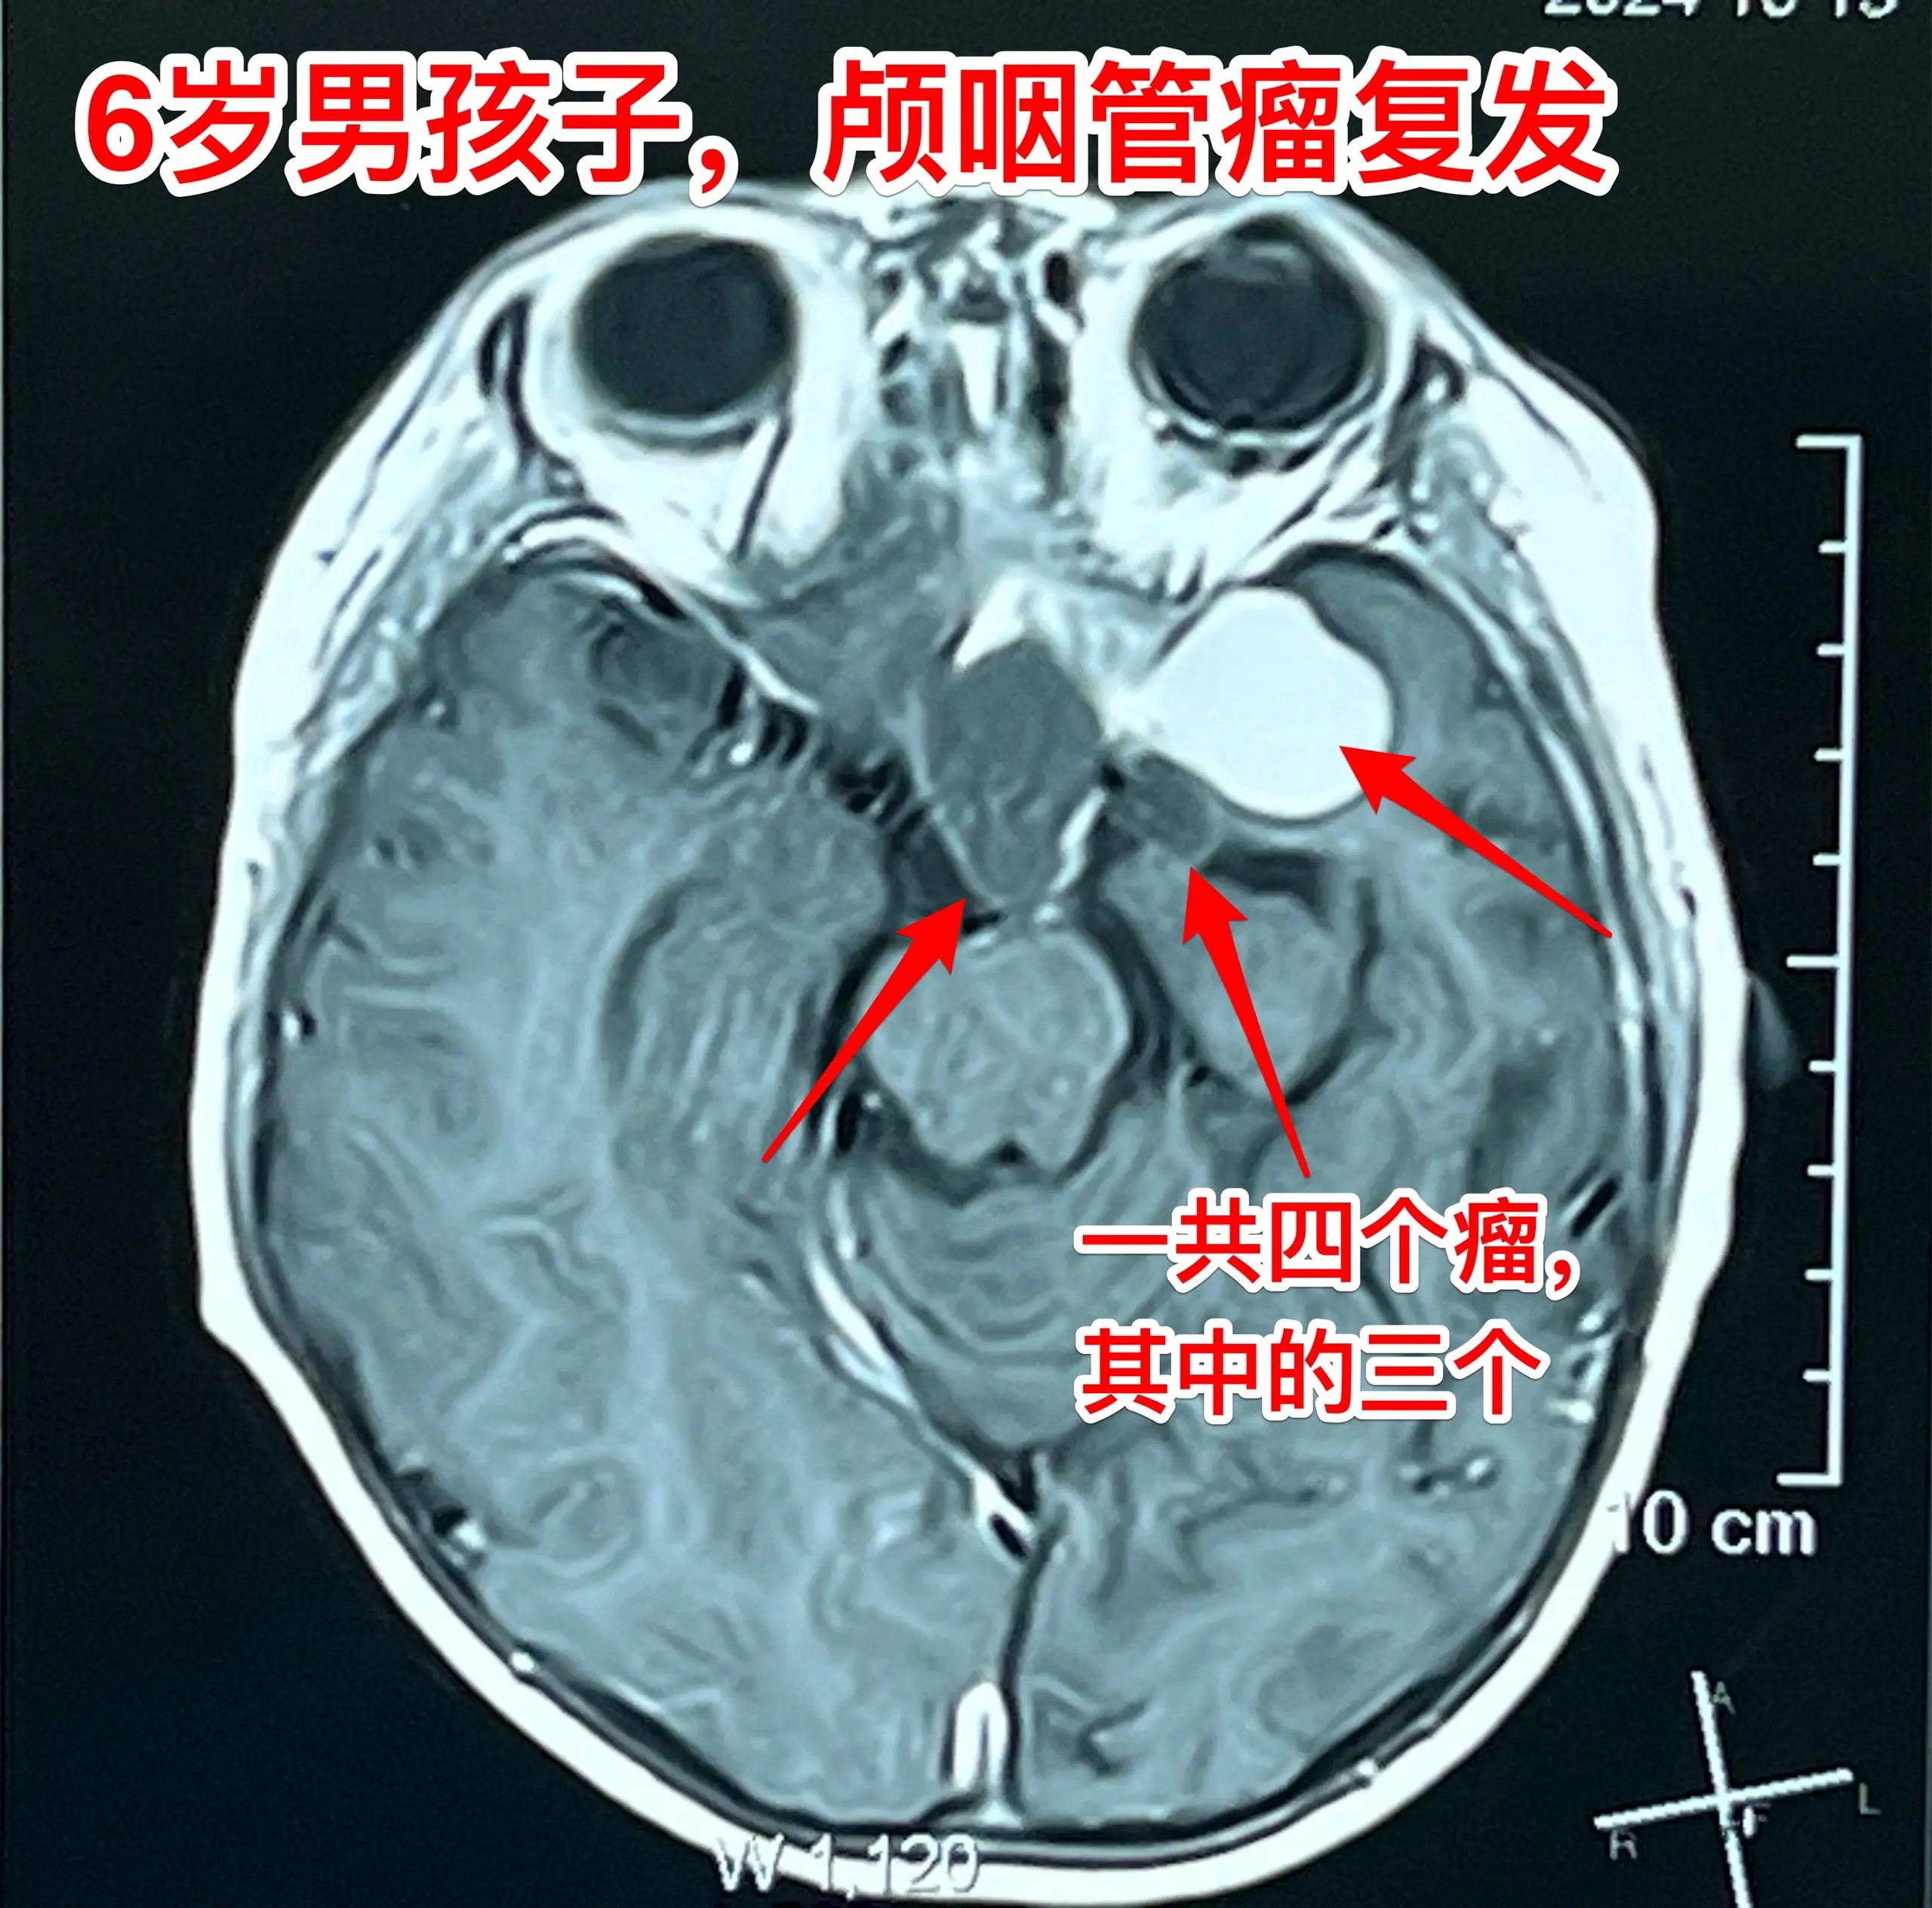

今日两个颅咽管瘤手术。1,6岁男孩子,安徽宿州人。2023年5月因视力下降发现了脑部长了巨大颅咽管瘤,见图1。家长曾经通过微信找我看过,最终选择在上海某医院行手术治疗,手术后出现右侧偏瘫,经过康复治疗后能勉强走路,但是右手还不能拿笔写字。2023.12磁共振就显示颅咽管瘤复发了(多块肿瘤复发)。2024.10又出现视力下降,故来找我作手术。今天手术中发现有四块较大的肿瘤,同时有很多个小钙化。所见肿瘤均顺利切除了。对比两次手术前的磁共振,可以说第一次手术更容易达到完全切除肿瘤,很遗憾,那一次机会错过了。 2,9岁男孩子,江苏盐城市的。因头痛、呕吐检查发现脑部有典型的颅咽管瘤,伴有脑积水。病人到我科住院后经用甘露醇和地塞米松后头痛、呕吐症状消失,能正常吃喝。今日作了开颅手术,顺利切除肿瘤。